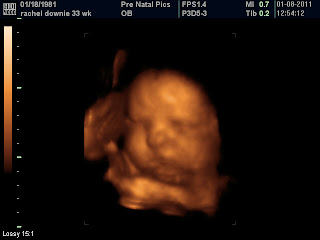

Now on to baby news....

So we had a doctor's appt today and my cervix has softened, but still not dialated. She evidently wants to stay in for a little while longer. James and I are both anxious to meet her. The doctor has said that if I do not go into labor on my own, that potentially he will induce on February 14th. So we may have a Valentine's Day baby if she doesn't decide to come earlier. I am hoping she comes soon it is definitely getting a little cramped in there...lol.